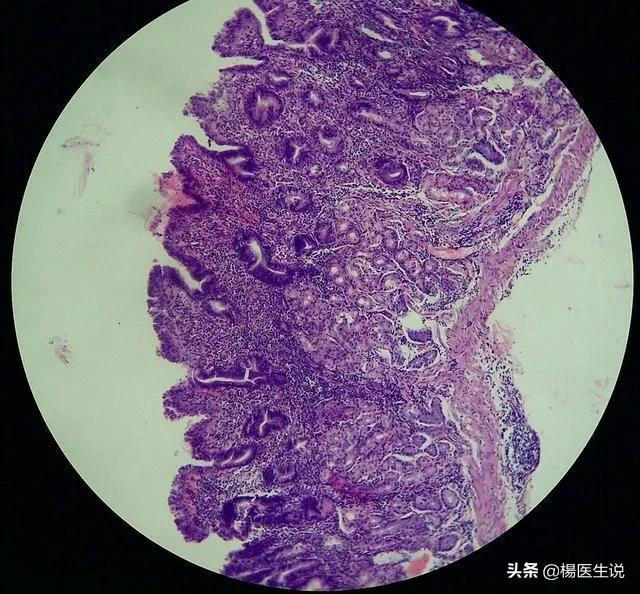

慢性萎縮性胃炎→胃がん

主な症状は、胃粘膜上皮および腺の萎縮、数の減少、胃粘膜の菲薄化である。患者は心窩部膨満感、腹部膨満感、腹鳴、食欲不振およびその他の症状を感じる。

簡単に言えば、様々な理由で胃粘膜が薄くなり、消化腺の消化液の分泌が減り、胃全体が萎縮するのではなく、胃が小さくなるのです。実際には、慢性萎縮性胃炎は55歳の人口に非常に一般的であり、検出率は50%以上であるため、中高年の萎縮のために、あまりにも心配する必要はありませんが、一部の医師は、それが退行性疾患と呼んでいる、つまり、人々は年を取ると、多かれ少なかれ、このような状況になります。

世界保健機関(WHO)は慢性萎縮性胃炎は胃癌の前癌病変に分類され、厳密には前癌ではないが、異型過形成の発生後に真に前癌となる。

萎縮性胃炎の発癌率は年間0.5~1%と報告されており、腸上皮過形成や異型過形成を伴うと胃癌のリスクが高まる。

萎縮性胃炎は多くの場合、腸炎になる前にピロリ菌を除菌することで回復させることができ、胃がんへの進行は対症療法と生活習慣の改善によってほぼ完全に阻止することができる。